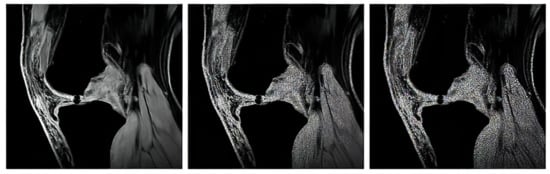

In our study, we use three variable sequences of articular cartilage, including T2-weighted images, proton density-weighted images, and gradient echo images. For each mentioned group, we tested in total of 1000 MR images from the public database Osteoarthritis Initiative (OAI) [71,72] to provide a robust comparison among individual segmentation approaches.

The proton density-weighted MR imaging is able to recognize in contrast the cartilage defects and abnormal cartilage composition in their tissues. This imaging sequence enables a suitable investigation of the cartilage morphology, ligaments, and menisci. The fat-saturated proton density-weighted images are suitable for the investigation of a low-signal intensities, which is a typical case of early cartilage loss. Therefore, this technique is well suited for the examination of osteoarthritis. As an example of the articular cartilage data, we provide a comparison of various sequences from the same cartilage area (Figure 4).

Proton density sequence plays an indispensable role in structural investigation of the early stage of articular cartilage loss. Here, only a weak contrast between a common cartilage surface and such pathological findings are notable. Therefore, for our analysis these data are substantially important. To objectivize such findings, we provide the example (Figure 5) from our dataset, where such investigations can be observed.